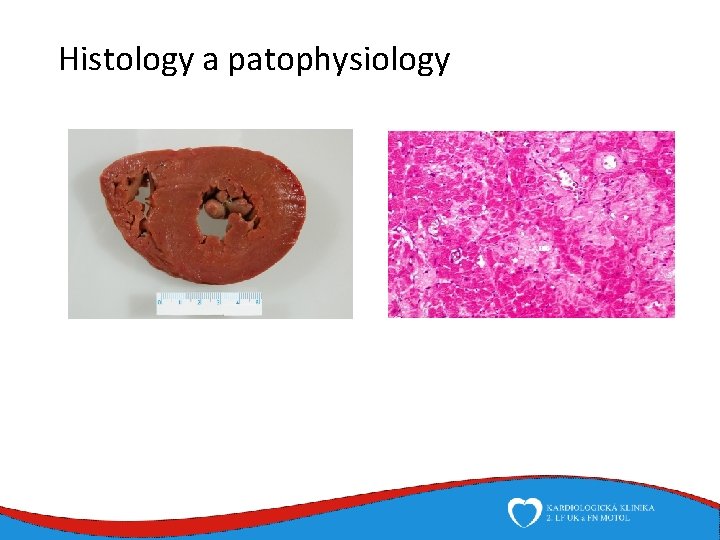

Histology a patophysiology